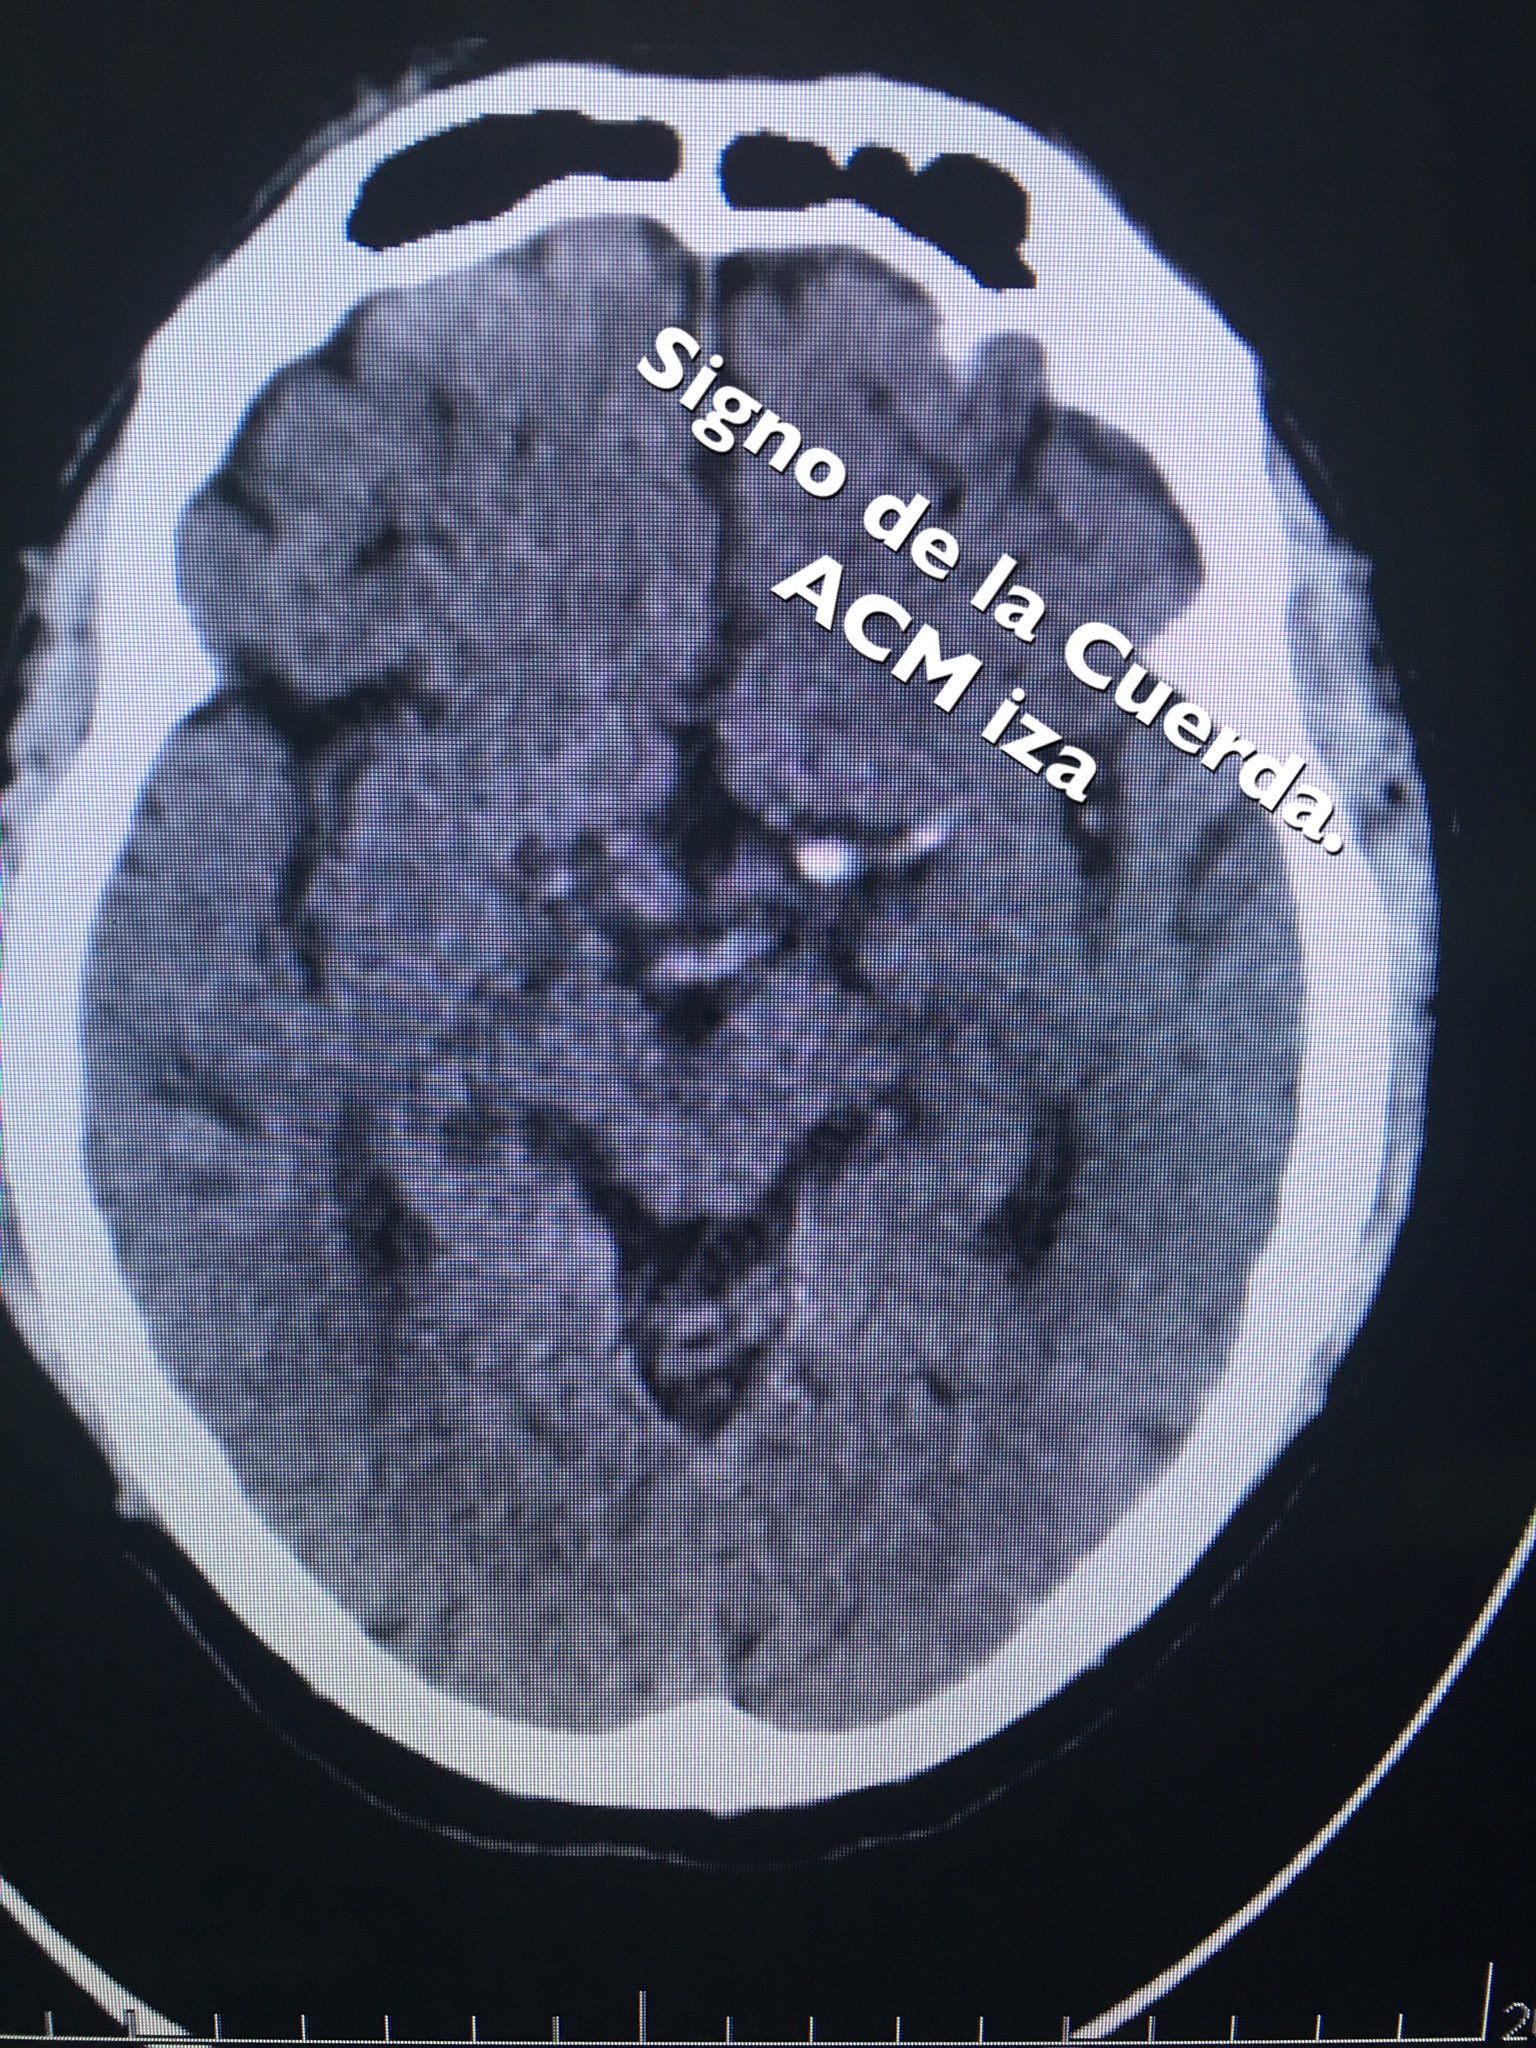

Se Observa El Signo De La Cuerda Dado Por La Hiperdensidad De La Download Scientific Diagram

Multimedia En Medicina 34 Signo De La Cuerda Interconsulta On Line

Ale Risso Vazquez على تويتر Pcte70 Anos Plejia Fbcder Afasia Expresion 1 Tac 2 Rnm Encefalo Signo De La Cuerda Imagenesenuti Le Chujte Acv